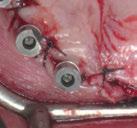

En las piezas 16 y 17 el paciente presentaba restauraciones atornilladas de metalcerámica sobre implantes oseointegrados. Se planificó realizar estas en una fase posterior a la rehabilitación de las piezas dentarias mediante flujo digital con bases de titanio y cuerpos de escaneo.

SW 5.2, Dentsply Sirona) (Figuras 22-27), la cual fue materializada en dos tipos de materiales a partir de bloques cerámicos IPS Empress CAD y cerámica vítrea de disilicato de litio IPS E.max CAD (Figuras 28-30)

Finalmente, las restauraciones se cementaron adhesivamente (Figuras 31-35). En las piezas 16 y 17 se realizaron restauraciones cementoatornilladas como última fase de tratamiento. Se recomendó al paciente una férula de protección superior la cual fue elaborada mediante un flujo de trabajo digital (Figura 36)